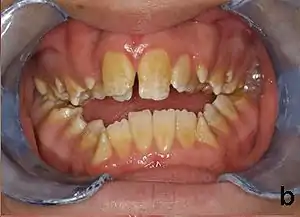

People afflicted with amelogenesis imperfecta may have teeth with abnormal color: yellow, brown or grey; this disorder can afflict any number of teeth of both dentitions. Enamel hypoplasia manifests in a variety of ways depending on the type of AI an individual has (see below), with pitting and plane-form defects common.[4] The teeth have a higher risk for dental cavities and are hypersensitive to temperature changes as well as rapid attrition, excessive calculus deposition, and gingival hyperplasia.[5] The earliest known case of AI is in an extinct hominid species called Paranthropus robustus, with over a third of individuals displaying this condition.[6]

AI can be classified according to their clinical appearances:[18]

- Type 1 - Hypoplastic

- Enamel of abnormal thickness due to malfunction in enamel matrix formation. Enamel is very thin but hard & translucent, and may have random pits & grooves. Condition is of autosomal dominant, autosomal recessive, or x-linked pattern. Enamel differs in appearance from dentine radiographically as normal functional enamel.[19]

- Type 2 - Hypomaturation

- Enamel has sound thickness, with a pitted appearance. It is less hard compared to normal enamel, and are prone to rapid wear, although not as intense as Type 3 AI. Condition is of autosomal dominant, autosomal recessive, or x-linked pattern. Enamel appears to be comparable to dentine in its radiodensity on radiographs.

- Type 3 - Hypocalcified

- Enamel defect due to malfunction of enamel calcification, therefore enamel is of normal thickness but is extremely brittle, with an opaque/chalky presentation. Teeth are prone to staining and rapid wear, exposing dentine. Condition is of autosomal dominant and autosomal recessive pattern. Enamel appears less radioopaque compared to dentine on radiographs.

- Type 4 - Hypomature hypoplastic enamel with taurodontism

- Enamel has a variation in appearance, with mixed features from Type 1 and Type 2 AI. All Type 4 AI has taurodontism in common. Condition is of autosomal dominant pattern. Other common features may include an anterior open bite,[20] taurodontism, sensitivity of teeth.